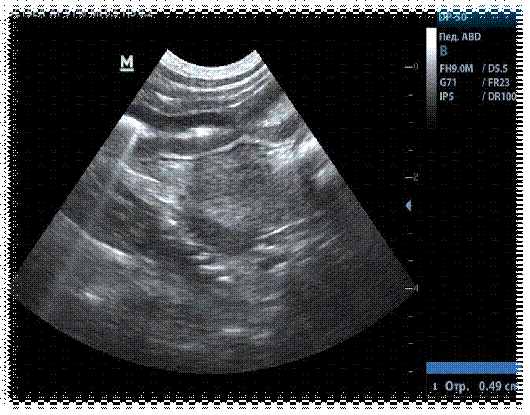

Ультразвуковое исследование брюшной полости.  Заключение: Желудок: форма - обычная, складки сохранены, не утолщены, эхогенность стенки нормальная. Тонкая кишка - моторика сохранена, стенка 0,3 см, не утолщена, эхогенность нормальная.

Заключение о проведенном УЗИ указывает на диффузное утолщение стенок желудка и тощей кишки без структурных изменений. Усиление перистальтики тонкого кишечника.

Животное пробыло на лечении 12 дней. Своевременно предпринятые терапевтические меры позволили значительно улучшить состояние здоровья пациента, что в конечном итоге привело к исчезновению признаков заболевания. Перед выпиской пациент повторно подвергся ультразвуковому исследованию брюшной полости (размеры стенок желудка и тощей кишки соответствуют норме до 0,3 мм), эффективность лечения подтверждена соответствующим заключением.

Рис.3 Сонография пилорического отдела желудка у кошки